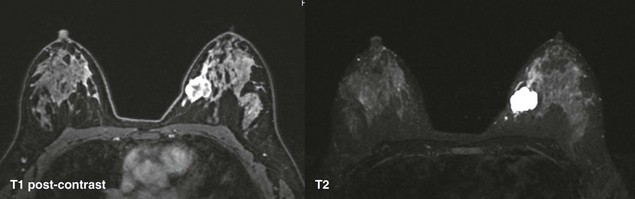

CASE 11-1. A 62-year-old woman with screening MRI. What is the most likely diagnosis of the left breast mass?

CASE 11-1. This is suspicious for a mucinous carcinoma. The mass is hyperintense on T2, but has heterogeneous enhancement and ill-defined margins. This should not be mistaken for a fibroadenoma.